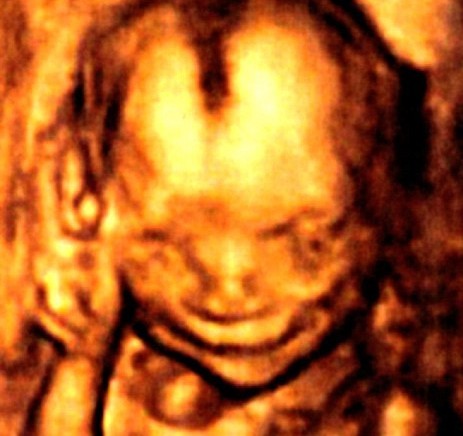

지난해 10월 임신한 루이스 부부는 임신 17주가 되던 때 초음파 검사를 하다 뱃속의 아이가 환하게 웃는 사실을 발견했다. 심지어 웃음 소리까지 들렸다고 루이스 부부는 전했다.

그동안 토토사이트 번호 차단가 웃는 것처럼 보이는 사진은 간혹 있었지만 이번 루이스 부부의 토토사이트 번호 차단처럼 분명히 ‘웃는 토토사이트 번호 차단’는 매우 이례적이라고 병원 측은 밝혔다.

영국의 산부인과 전문의 캠벨은 “40년 의사 경력 동안 17주된 토토사이트 번호 차단가 웃는 것은 보지 못했다”며 “이는 분명 토토사이트 번호 차단가 감정을 느끼는 것을 뒷받침하는 것”이라고 말했다.